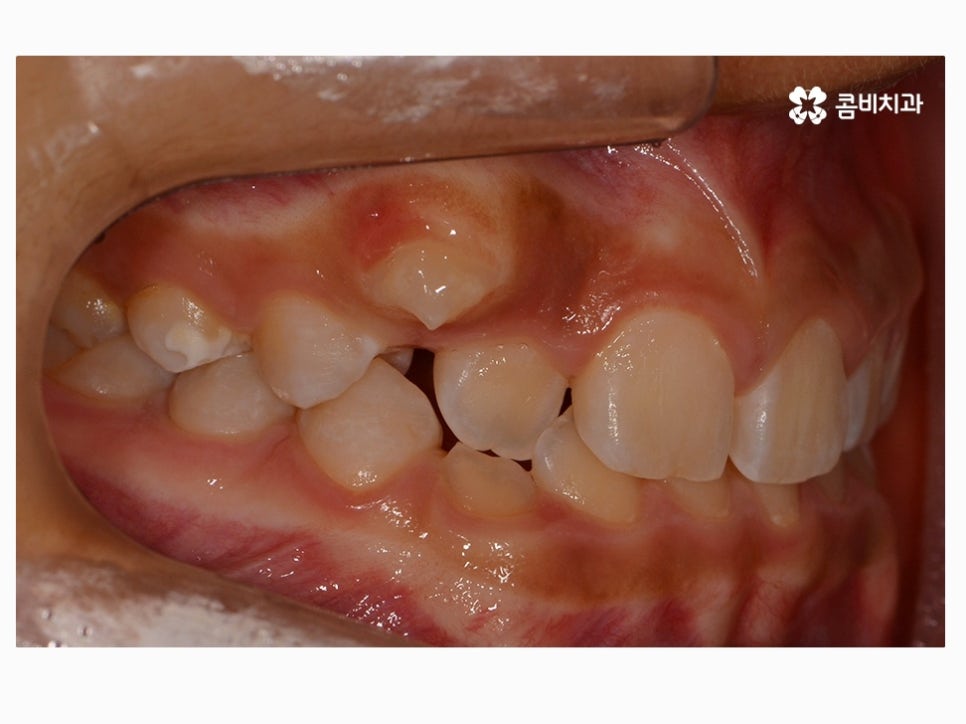

부정교합을 치료하는 방법은 나이대와 어떤 상태인지 진단에

따라서 달라질 수 있는데 위 케이스처럼 일반적인 치아교정으로

진행이 되는 경우도 있고 구외 교정 장치를 활용하는 경우 등 진단에 따라 다양할 수 있어요.